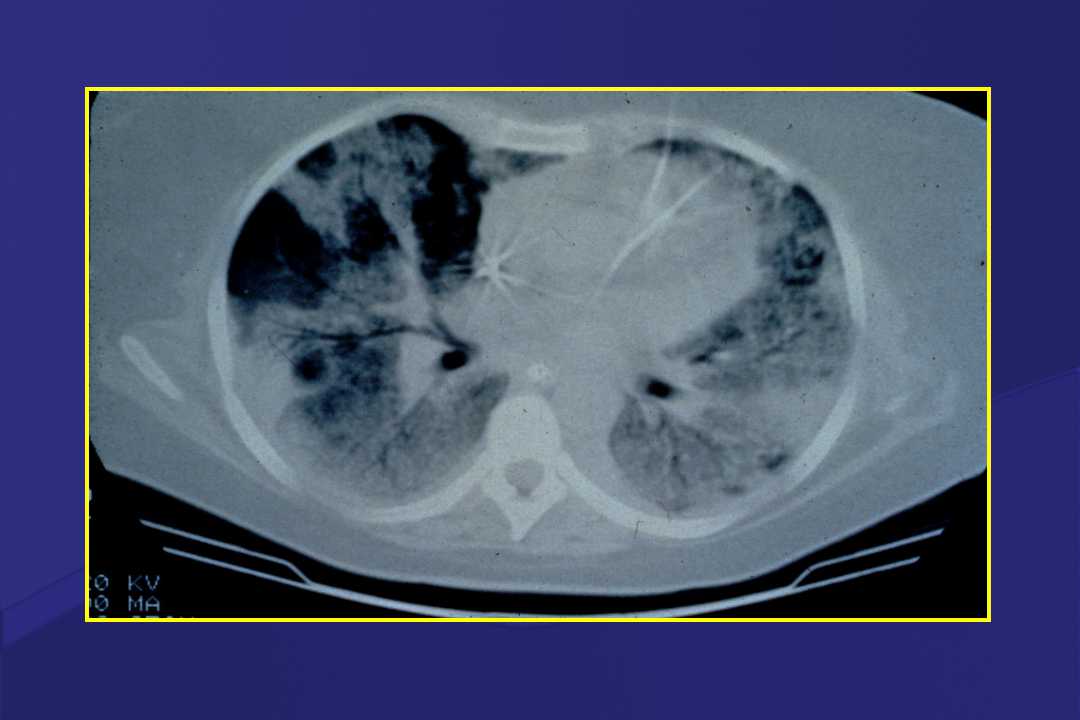

血液疾病患者肺部并发症影像学表现